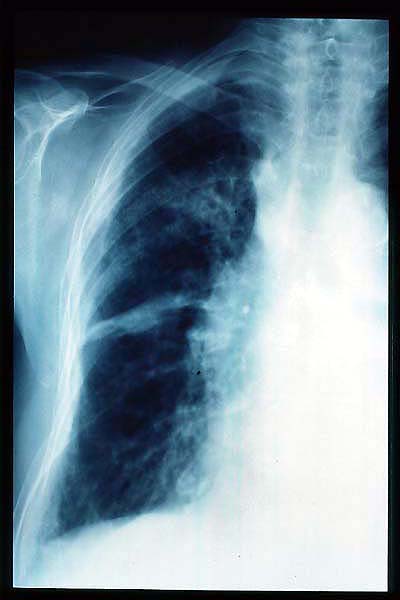

Calcificación de aórtica torácica.

Osteoporosis. Cifosis.

Deformidad torácica.

Fibrosis pulmonar. ICC.